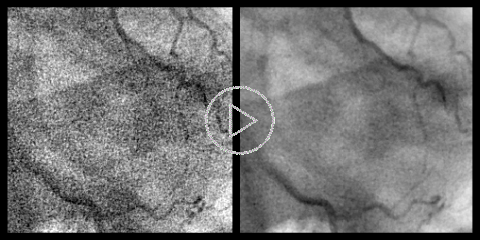

Temporal Filter (Synthetic Exposure):

The temporal filter takes advantage of our flexible image registration algorithm. For every new frame, a user selected number of past frames are warped to match the current one to one-tenth of the pixel size. Warped frames are then added together within the temporal bilateral filter. This reduces noise and for cases where a reasonably good match can be obtained it has the effect of accumulated pixel exposure, thus we coined the term "Synthetic Exposure".In this example the images, as you see on the left, was first contrast enhanced by aggressive LOW filter and edge enhancement. This creates series of very grainy images, which are then filtered by the strong temporal filter. This example is definitely an exaggeration, but was chosen to illustrate the results that clearly cannot be achieved by spatial filtering. |